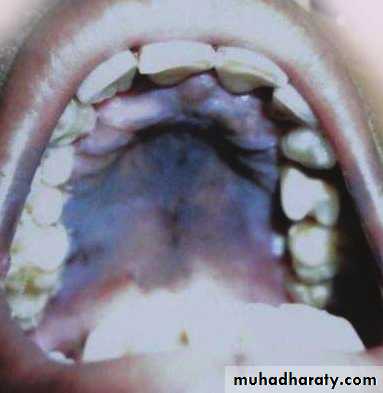

The Skin in Diabetes Mellitus:1- Necrobiosis lipoidica.2- Diabetic dermopathy (shin spots).3- Neuropathic foot ulcers.4- Infections: candidal, staphylococcal, and non clostridial gangrene.5- Diabetic bullae.6- Stiff thick skin (diabetic cheiroarthropathy).7- Carotenodermia (yellow skin).8- Diabetic rubeosis of the face).9- Granuloma annulare.10- Pruritus.11- Eruptive xanthoma.12- Acanthosis nigricans.13- Skin tags.